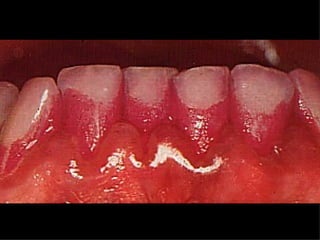

LESIÓN INCIPIENTE DE

SUPERFICIE LISA

   El primer indicio es una

mancha blanca por

vestibular o lingual

   Tienen color blanco gredoso

al desecar

   La mancha blanca de caries

incipientes desaparece al

humedecer

   La mancha blanca de la

hipocalcificación del esmalte

no desaparece ni al

humedecer ni al secarse

   Una lesión inicial tiene textura superficial

inalterable

   Una lesión avanzada desarrolla superficie

irregular que si desconcha con el explorador es

caries activa

   La lesión incipiente se puede remineralizar a

traves de los iones de calcio y fosfato de la saliva

junto con la presencia de fluor formando

fluorapatita

   Clínicamente son de color pardo o negrusco, son

más resistente que el esmalte sano y no deben

restaurarse salvo por razones estética